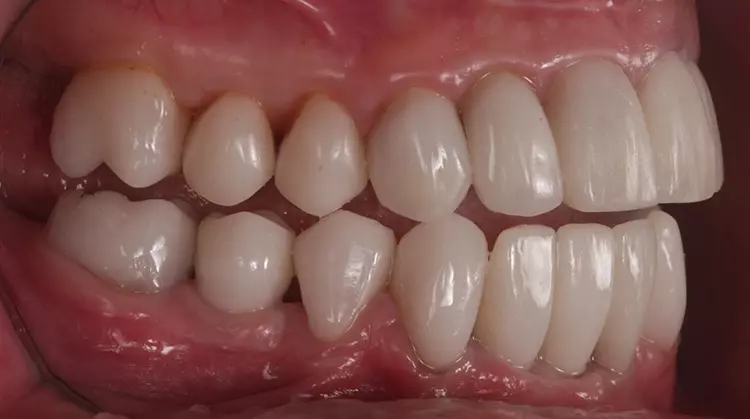

Der Unterkiefer „arbeitet“ nach Abschluss der Rekonstruktion „interferenzfreier“ und „muskulär koordinierter“ als je zuvor, was für die Kaumuskulatur weniger Kraftaufwand (keine Vermeidungs- und Ausweichbewegungen) und mehr Effizienz (verbesserte Okklusion und Artikulation, Abb. 15 bis 17) bedeutet. Dies ist der Therapieplanung (im Sinne eines „Backward-Planning) und deren gezielter Umsetzung und somit hoher Vorhersagbarkeit für eine langfristige Prognose der Rekonstruktion zuzusprechen. Im Molarenbereich zeigen sich noch dynamische Kontakte, insbesondere bei parafunktioneller Aktivität (Abb. 18), die sich auch im Erscheinungsbild der Condylografie-Kurven widerspiegeln.

Aufgrund der klinischen Beschwerdefreiheit und auch der Tatsache, dass Heilungs- und Umbauvorgänge im Gelenk noch stattfinden können, soll vorerst noch 6 bis12 Monate bei regelmäßiger klinischer Nachkontrolle abgewartet werden. Die Patientin ist subjektiv beschwerdefrei (keine Anzeichen einer Dekompensation in der klinischen Funktionsanalyse). Zudem äußert sie keine Druckdolenz der Kaumuskulatur und/oder der Gelenke [22,23] (Abb. 19 bis 22).